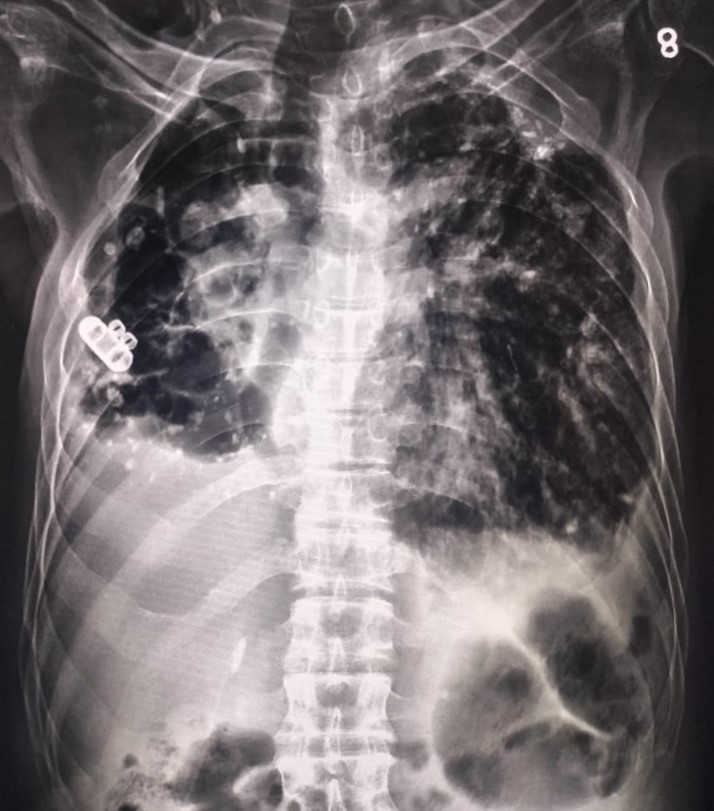

| 197 | IGGMC, Nagpur, Nagpur | P2 | 29-4275 | Meerabai Kuril | Consent taken on Paper | 58 Yrs. |

Provisional Diag : Post TB Bronchiectasis?

Final Diag : Post TB Sequeale (CxR- Bilateral Fibro cavitary Changer) |

Post TB Sequelae | CxR- Bilateral Fibro cavitary Changer | Abnormality visible on x-ray |